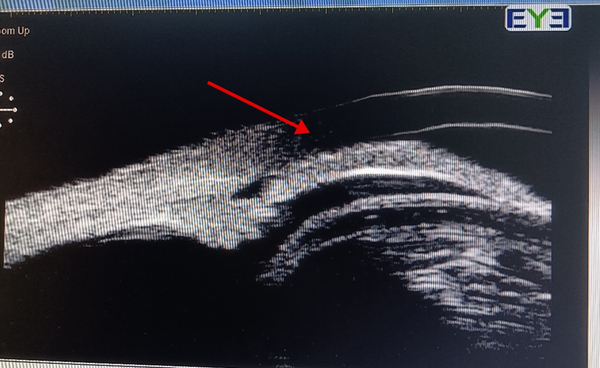

UBM检查显示,膨胀变大的晶状体挤压前房,导致房角变窄阻碍房水流通,极易导致青光眼的发生。

▲ 晶状体膨胀后的房角闭合状态

被挤压的前房深度只剩1.21mm,让晶状体和角膜的空间变得极度狭窄。手术过程中使器械操作空间受限,稍有不慎,就可能对角膜、瞳孔等造成伤害。

这些变化导致手术难度和风险呈几何级数增加。